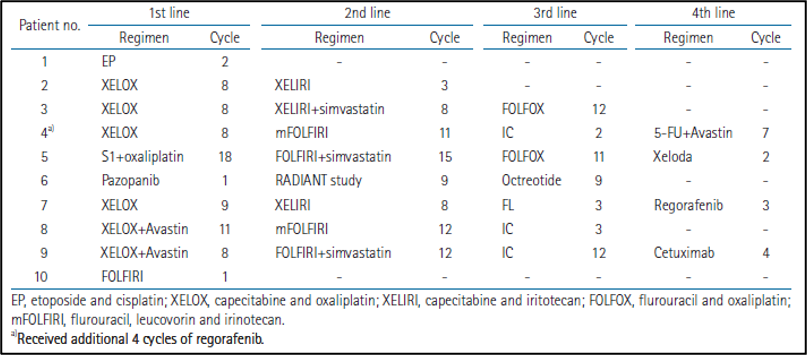

הטיפול הקודם

המספר החציוני של מחזורי כימותרפיה שניתנו לפני הרישום למחקר היה 23 (טווח של 1 עד 46).נעשה שימוש ביותר מ-10 מחזורים של כימותרפיה, למעט בשני מטופלים עם התקדמות נרחבת של גרורות בכבד לאחר התחלת משטר הכימותרפיה הראשון. מטופלים אלו לא יכלו לקבל כימותרפיה נוספת בשל החמרה בתפקודי הכבד. משטרי טיפול הכימותרפיה הנפוצים היו קפציטבין (capecitabine) ואוקסליפלטין (oxaliplatin) או פלואורואורציל (5-fluorouracil), עם לויקובורין (leucovorin) ואירינוטקאן (irinotecan) עבור אדנוקרצינומה (adenocarcinoma) או אטופוסיד (etoposide) עם ציספלטין (cisplatin) או אוקטריאוטיד (octreotide) עבור קרצינומה נוירואנדוקרינית (neuroendocrine carcinoma). משטרי כימותרפיה מפורטים מוצגים בטבלה משלימה 3. רדיותרפיה פליאטיבית (Palliative RT) ניתנה לשני מטופלים עם מסות ראשוניות (primary masses) ולמטופל אחד עם גרורות בעמוד השדרה (spine metastasis) עם דחיסה של חוט השדרה (spinal cord compression).

להלן טבלה משלימה 3: משטרי כימותרפיה מפורטים של המטופלים הרשומים